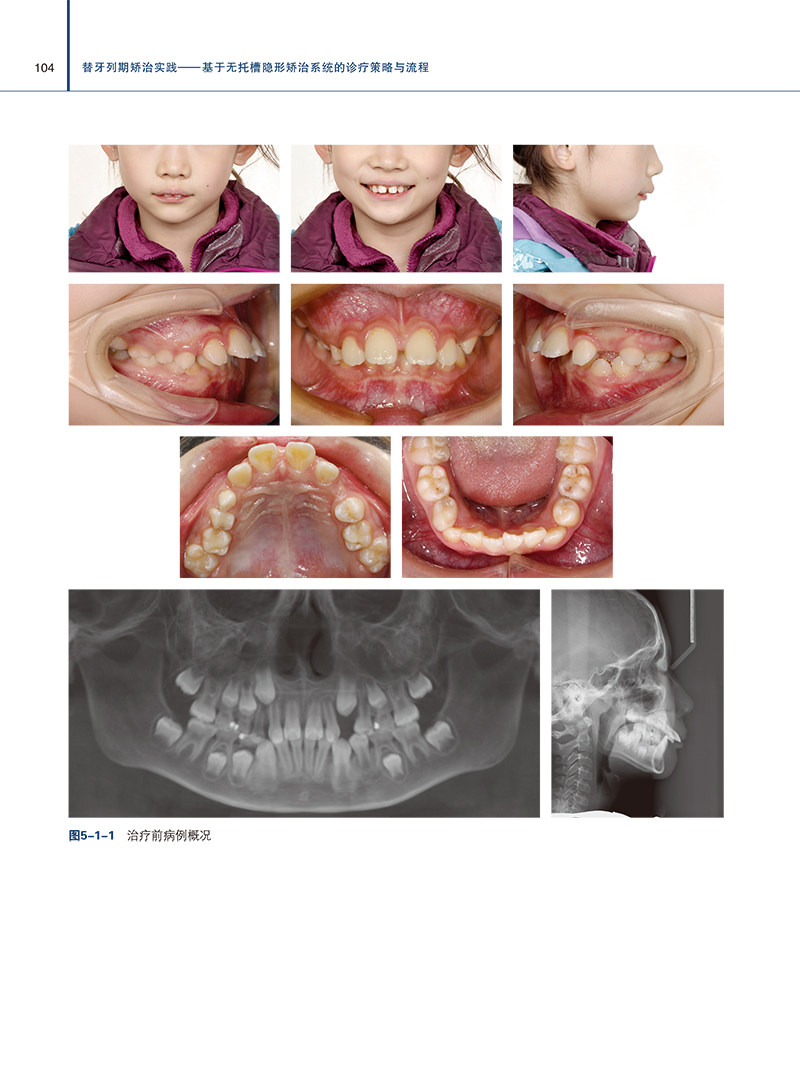

本书是一本专注于无托槽隐形矫治技术的权威著作。书中汇集前沿隐形矫治策略与临床实践,深度解析替牙列期错畸形的诊疗流程。通过丰富的病例分析,揭示生长发育规律,提供科学、精准的治疗指导。本书以实战为导向,为口腔正畸医生提供即学即用的知识宝库,是提升临床技能、优化患者治疗效果的推荐参考书。